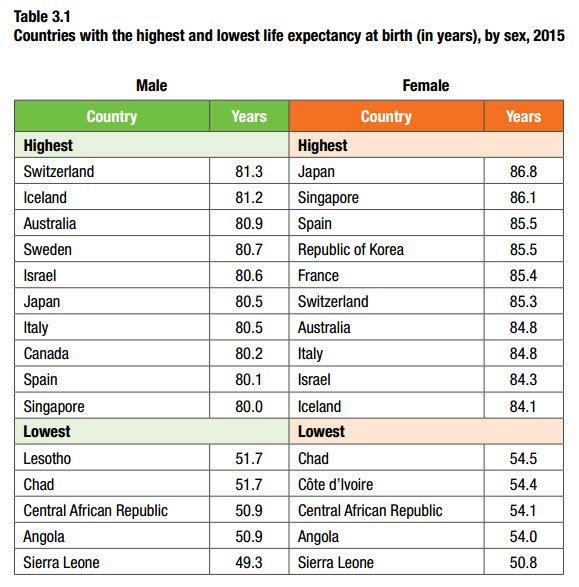

WHO report finds life expectancy increased by 5 years since 2000 http://bit.ly/1U7H3E3 pic.twitter.com/V5wmdnDwUE

06:33 ಪೂರ್ವಾಹ್ನ - ಮೇ 24,2016 · ವಿವರಗಳು17 ಮರುಟ್ವೀಟಿಸುವಿಕೆಗಳು 15ಇಷ್ಟಗಳು

06:33 ಪೂರ್ವಾಹ್ನ - ಮೇ 24,2016 · ವಿವರಗಳು17 ಮರುಟ್ವೀಟಿಸುವಿಕೆಗಳು 15ಇಷ್ಟಗಳು -